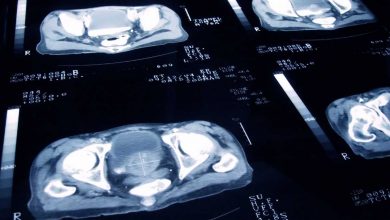

Esta enfermedad es una de las que más cobra vidas a nivel mundial. Radiografía de un examen de Cáncer de…